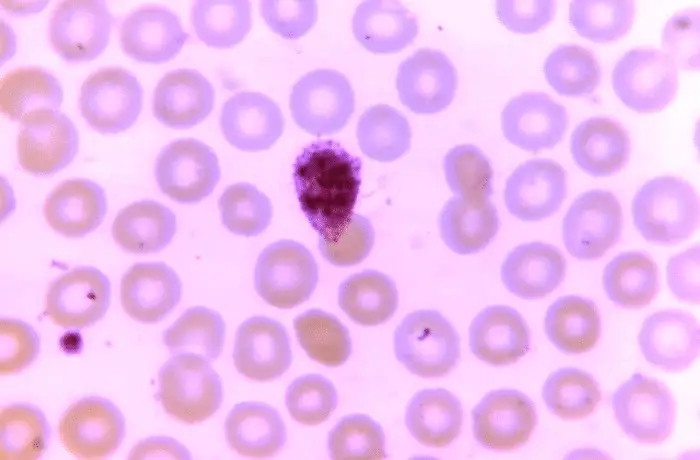

La malaria resta una delle malattie infettive più letali al mondo. È causata da parassiti del genere Plasmodium, che si moltiplicano rapidamente sia nell’uomo sia nelle zanzare. Comprendere in dettaglio come questi organismi si dividono e si riproducono è essenziale per sviluppare strategie realmente efficaci contro la malattia.

Negli esperimenti di laboratorio, la disattivazione della proteina ha portato a un rapido collasso dello sviluppo del parassita. Senza ARK1, il Plasmodium non riesce a formare correttamente il fuso mitotico e quindi non può dividersi in modo efficace.

Il risultato è netto: il parassita non completa il proprio ciclo vitale né nell’uomo né nella zanzara, interrompendo di fatto la catena di trasmissione della malaria.